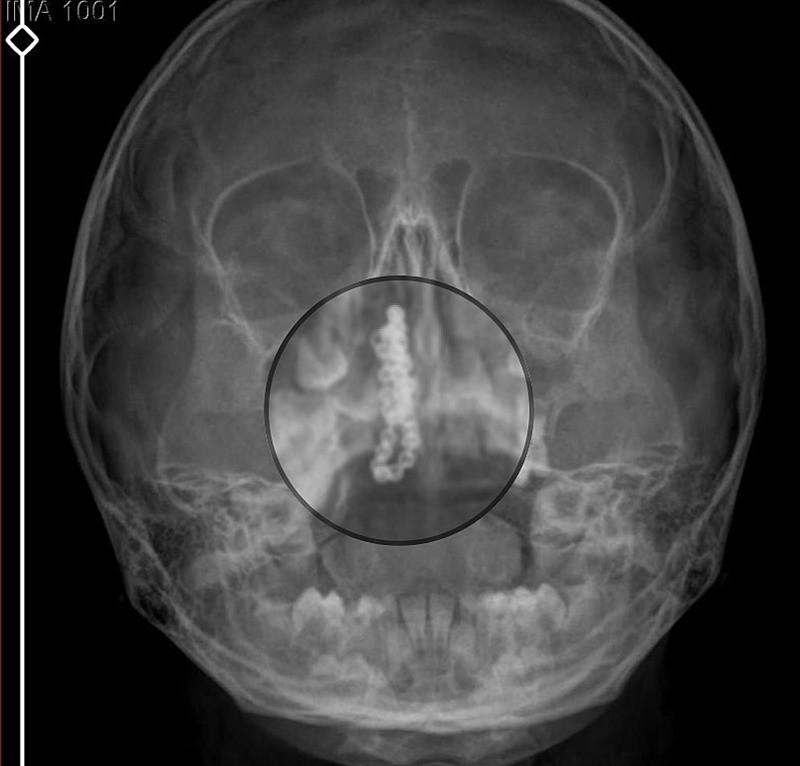

Burada röntgeni çekilip, tetkikleri tamamlanan küçük kıza, iddiaya göre enfeksiyon teşhisi konulup, ilaç verildi. Eve dönen aile, kanama ve akıntının geçmemesi üzerine bu kez Rize Devlet Hastanesi'ne giderek Kulak Burun Boğaz Polikliniği'ne başvurdu.

Rize'de özel hastanenin röntgene rağmen 'enfeksiyon' teşhisi koyup eve gönderdiği 5 yaşındaki çocuğun burnundan, devlet hastanesindeki detaylı incelemede 2 yıllık tırnak makası zinciri çıkarıldı (Fotoğraflar DHA'dan alınmıştır)

Devlet hastanesindeki doktorun incelemesi ve kapsamlı röntgen çekilmesi sonrası Polen'in burnunda metal cisim olduğu fark edildi. 2 yıldır burunda kaldığı değerlendirilip, küçük top şeklinde tırnak makası zinciri olduğu belirlenen cisim, başarılı ameliyatla çıkarıldı. Bir süre tedavisi sürdürülen Polen, sağlığına kavuşunca taburcu edildi. Özel hastane yetkilileri, konuyla ilgili açıklama yapmazken; aile suç duyurusunda bulunacaklarını söyledi.